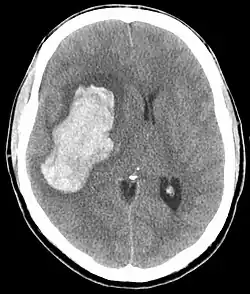

CT scan depicting intracranial hemorrhage, a possible complication of hypertensive emergency. Patients with spontaneous intracranial hemorrhage present with newfound headache and neurologic deficits. | |

- Abnormal sensations

In the brain, hypertensive encephalopathy - characterized by hypertension, altered mental status, and swelling of the optic disc - is a manifestation of the dysfunction of cerebral autoregulation. Cerebral autoregulation is the ability of the blood vessels in the brain to maintain a constant blood flow. People with chronic hypertension can tolerate higher arterial pressure before their autoregulation system is disrupted. Hypertensives also have an increased cerebrovascular resistance which puts them at greater risk of developing cerebral ischemia if the blood flow decreases into a normotensive range. On the other hand, sudden or rapid rises in blood pressure may cause hyperperfusion and increased cerebral blood flow, causing increased intracranial pressure and cerebral edema, with increased risk of intracranial bleeding.[7]

Consequences of hypertensive emergency result after prolonged elevations in blood pressure and associated end-organ dysfunction. Acute end-organ damage may occur, affecting the neurological, cardiovascular, kidney, or other organ systems. Some examples of neurological damage include hypertensive encephalopathy, cerebral vascular accident/cerebral infarction, subarachnoid hemorrhage, and intracranial bleeding. Cardiovascular system damage can include myocardial ischemia/infarction, acute left ventricular dysfunction, acute pulmonary edema, and aortic dissection. Other end-organ damage can include acute kidney failure or insufficiency, retinopathy, eclampsia, lung cancer, brain cancer, leukemia and microangiopathic hemolytic anemia.